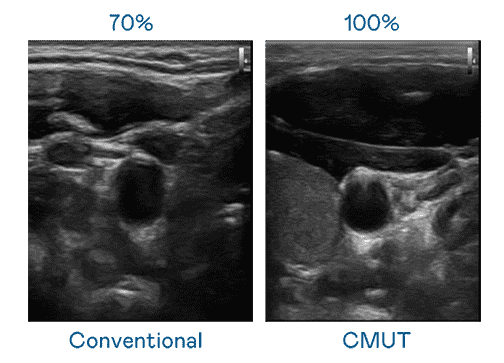

CMUT 技术是一种用电容式微机电元件来产生超音波讯号的技术。。与传统 PZT 压电式技术相比,,CMUT 频宽增加 30%,,更宽频的超音波讯号让影像解析度大幅提升,,,是实现高影像品质医疗超音波扫描、、促进精准医疗发展的关键技术。。

大频宽带来超清晰影像

超音波影像的解析度高低,,首先取决于探头能发出的讯号频宽。。。。糖果派对 CMUT 可提供高清晰的超音波讯号,,,,提供高频宽、、高灵敏度、、、、影像纹理细节更高的超音波影像,,,,协助医护人员缩短影像判读时间及利用精准的医疗影像进行诊断。。。。